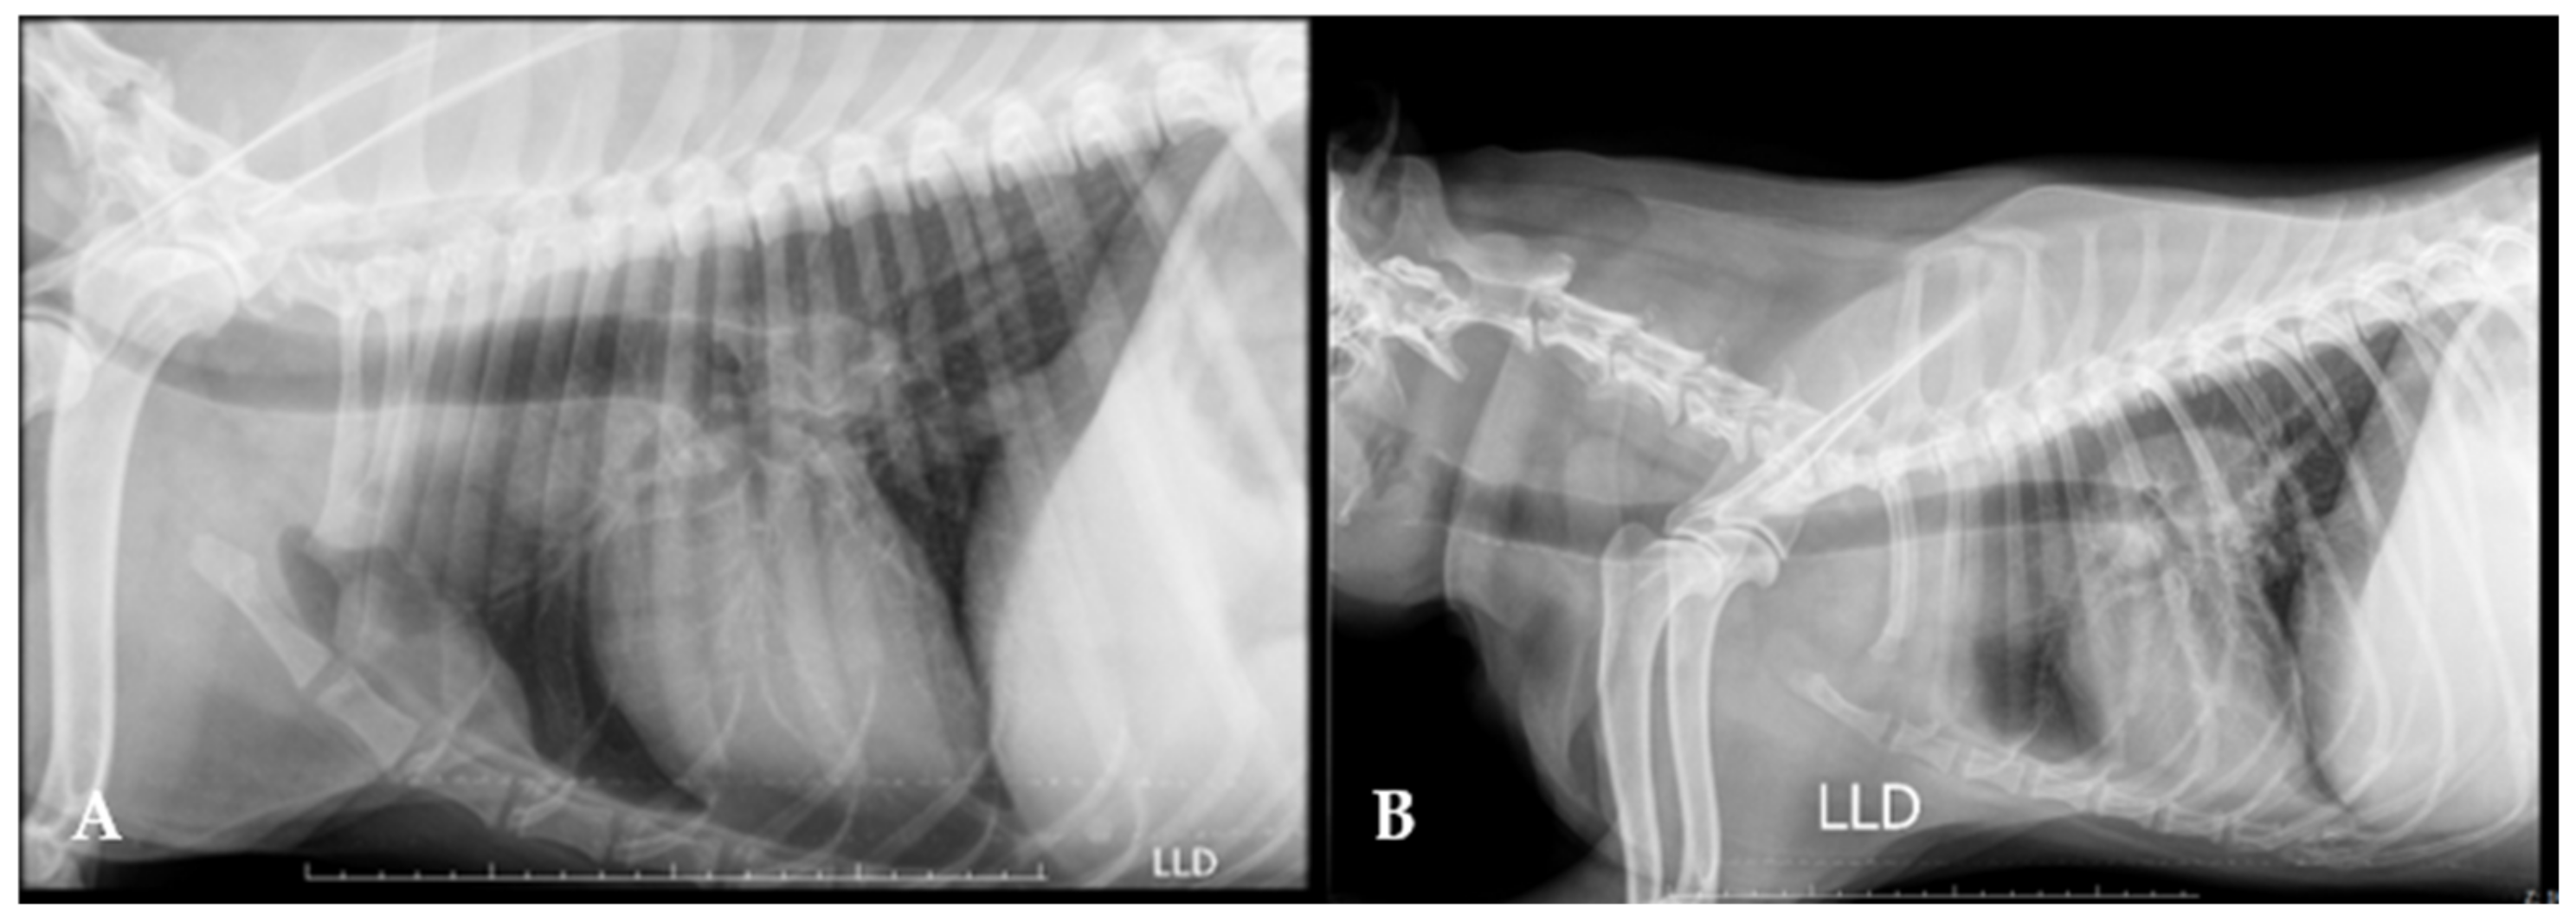

3.6. Diagnostic Imaging